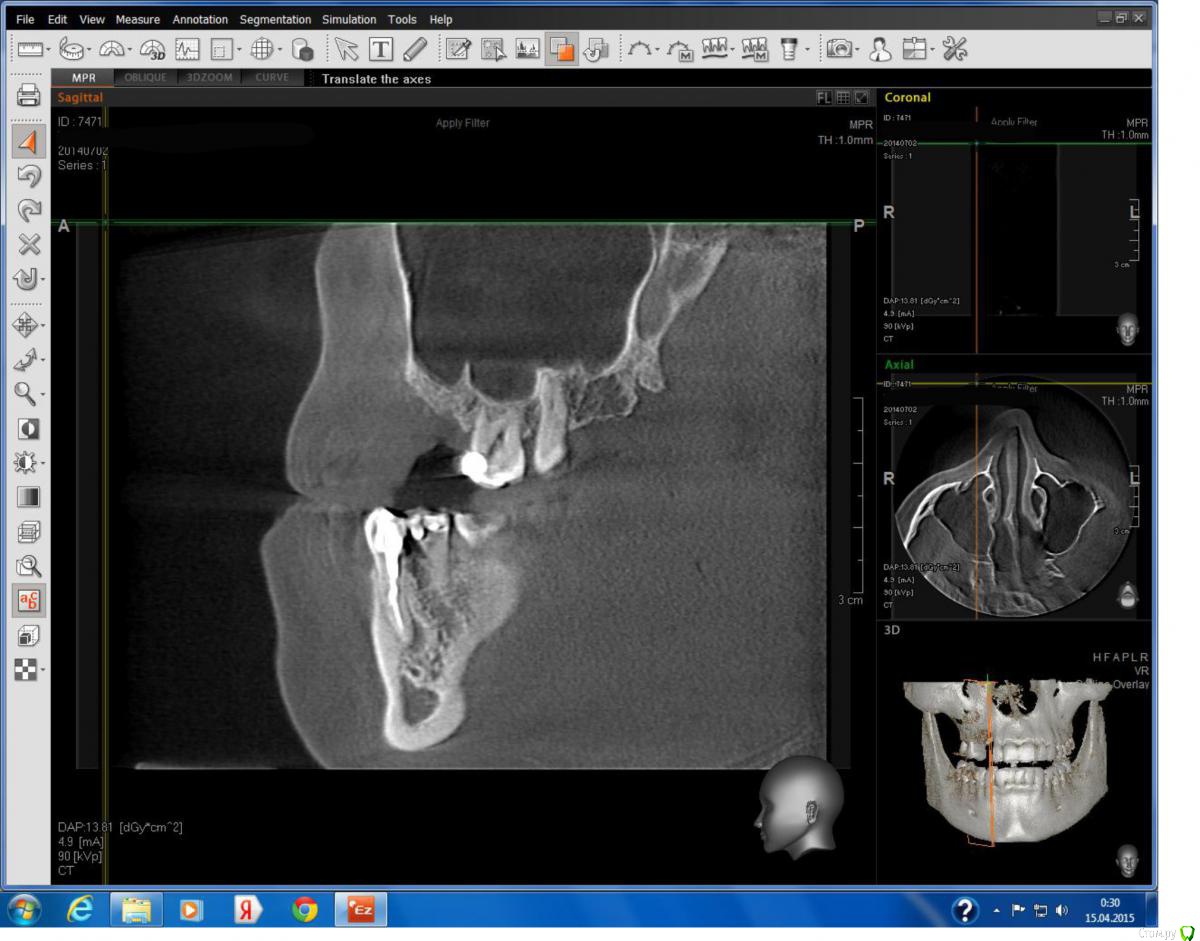

Lollipop Опубликовано 14 апреля, 2015 Поделиться Опубликовано 14 апреля, 2015 Добрый вечер!Зуб 4.4, было 2 раза эндолечение, в результате второго прохождения канала, на верхушке корня образовалась киста. Предложена имплантация. Может можно обойтись менее радикальными методами лечения? Заранее большое спасибо. Ссылка на комментарий

Lollipop Опубликовано 14 апреля, 2015 Автор Поделиться Опубликовано 14 апреля, 2015 Прицельного снимка к сожалению нет, вот другой срез КТ, вроде получше видно. Ссылка на комментарий

DmitrySH Опубликовано 14 апреля, 2015 Поделиться Опубликовано 14 апреля, 2015 Сам очаг воспаления не так уж и страшен. Нужно убирать все пломбы с зуба, смотреть что остается и можно ли потом сделать адекватное ортопедическое восстановление Ссылка на комментарий